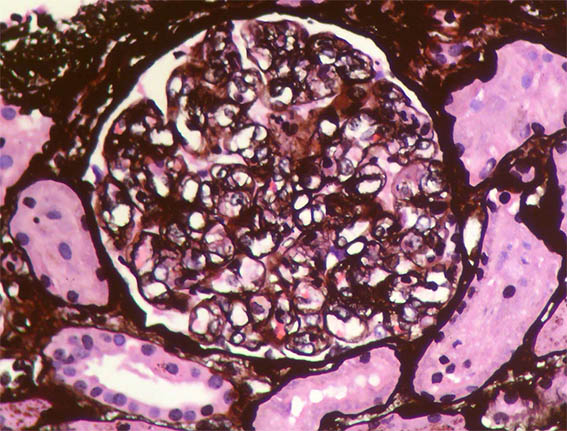

Figure 7. Methenamine-silver stain, X400. More intracapillary hyaline material and some double contours.

Figure 8. Methenamine-silver stain, X400. Some double contours.